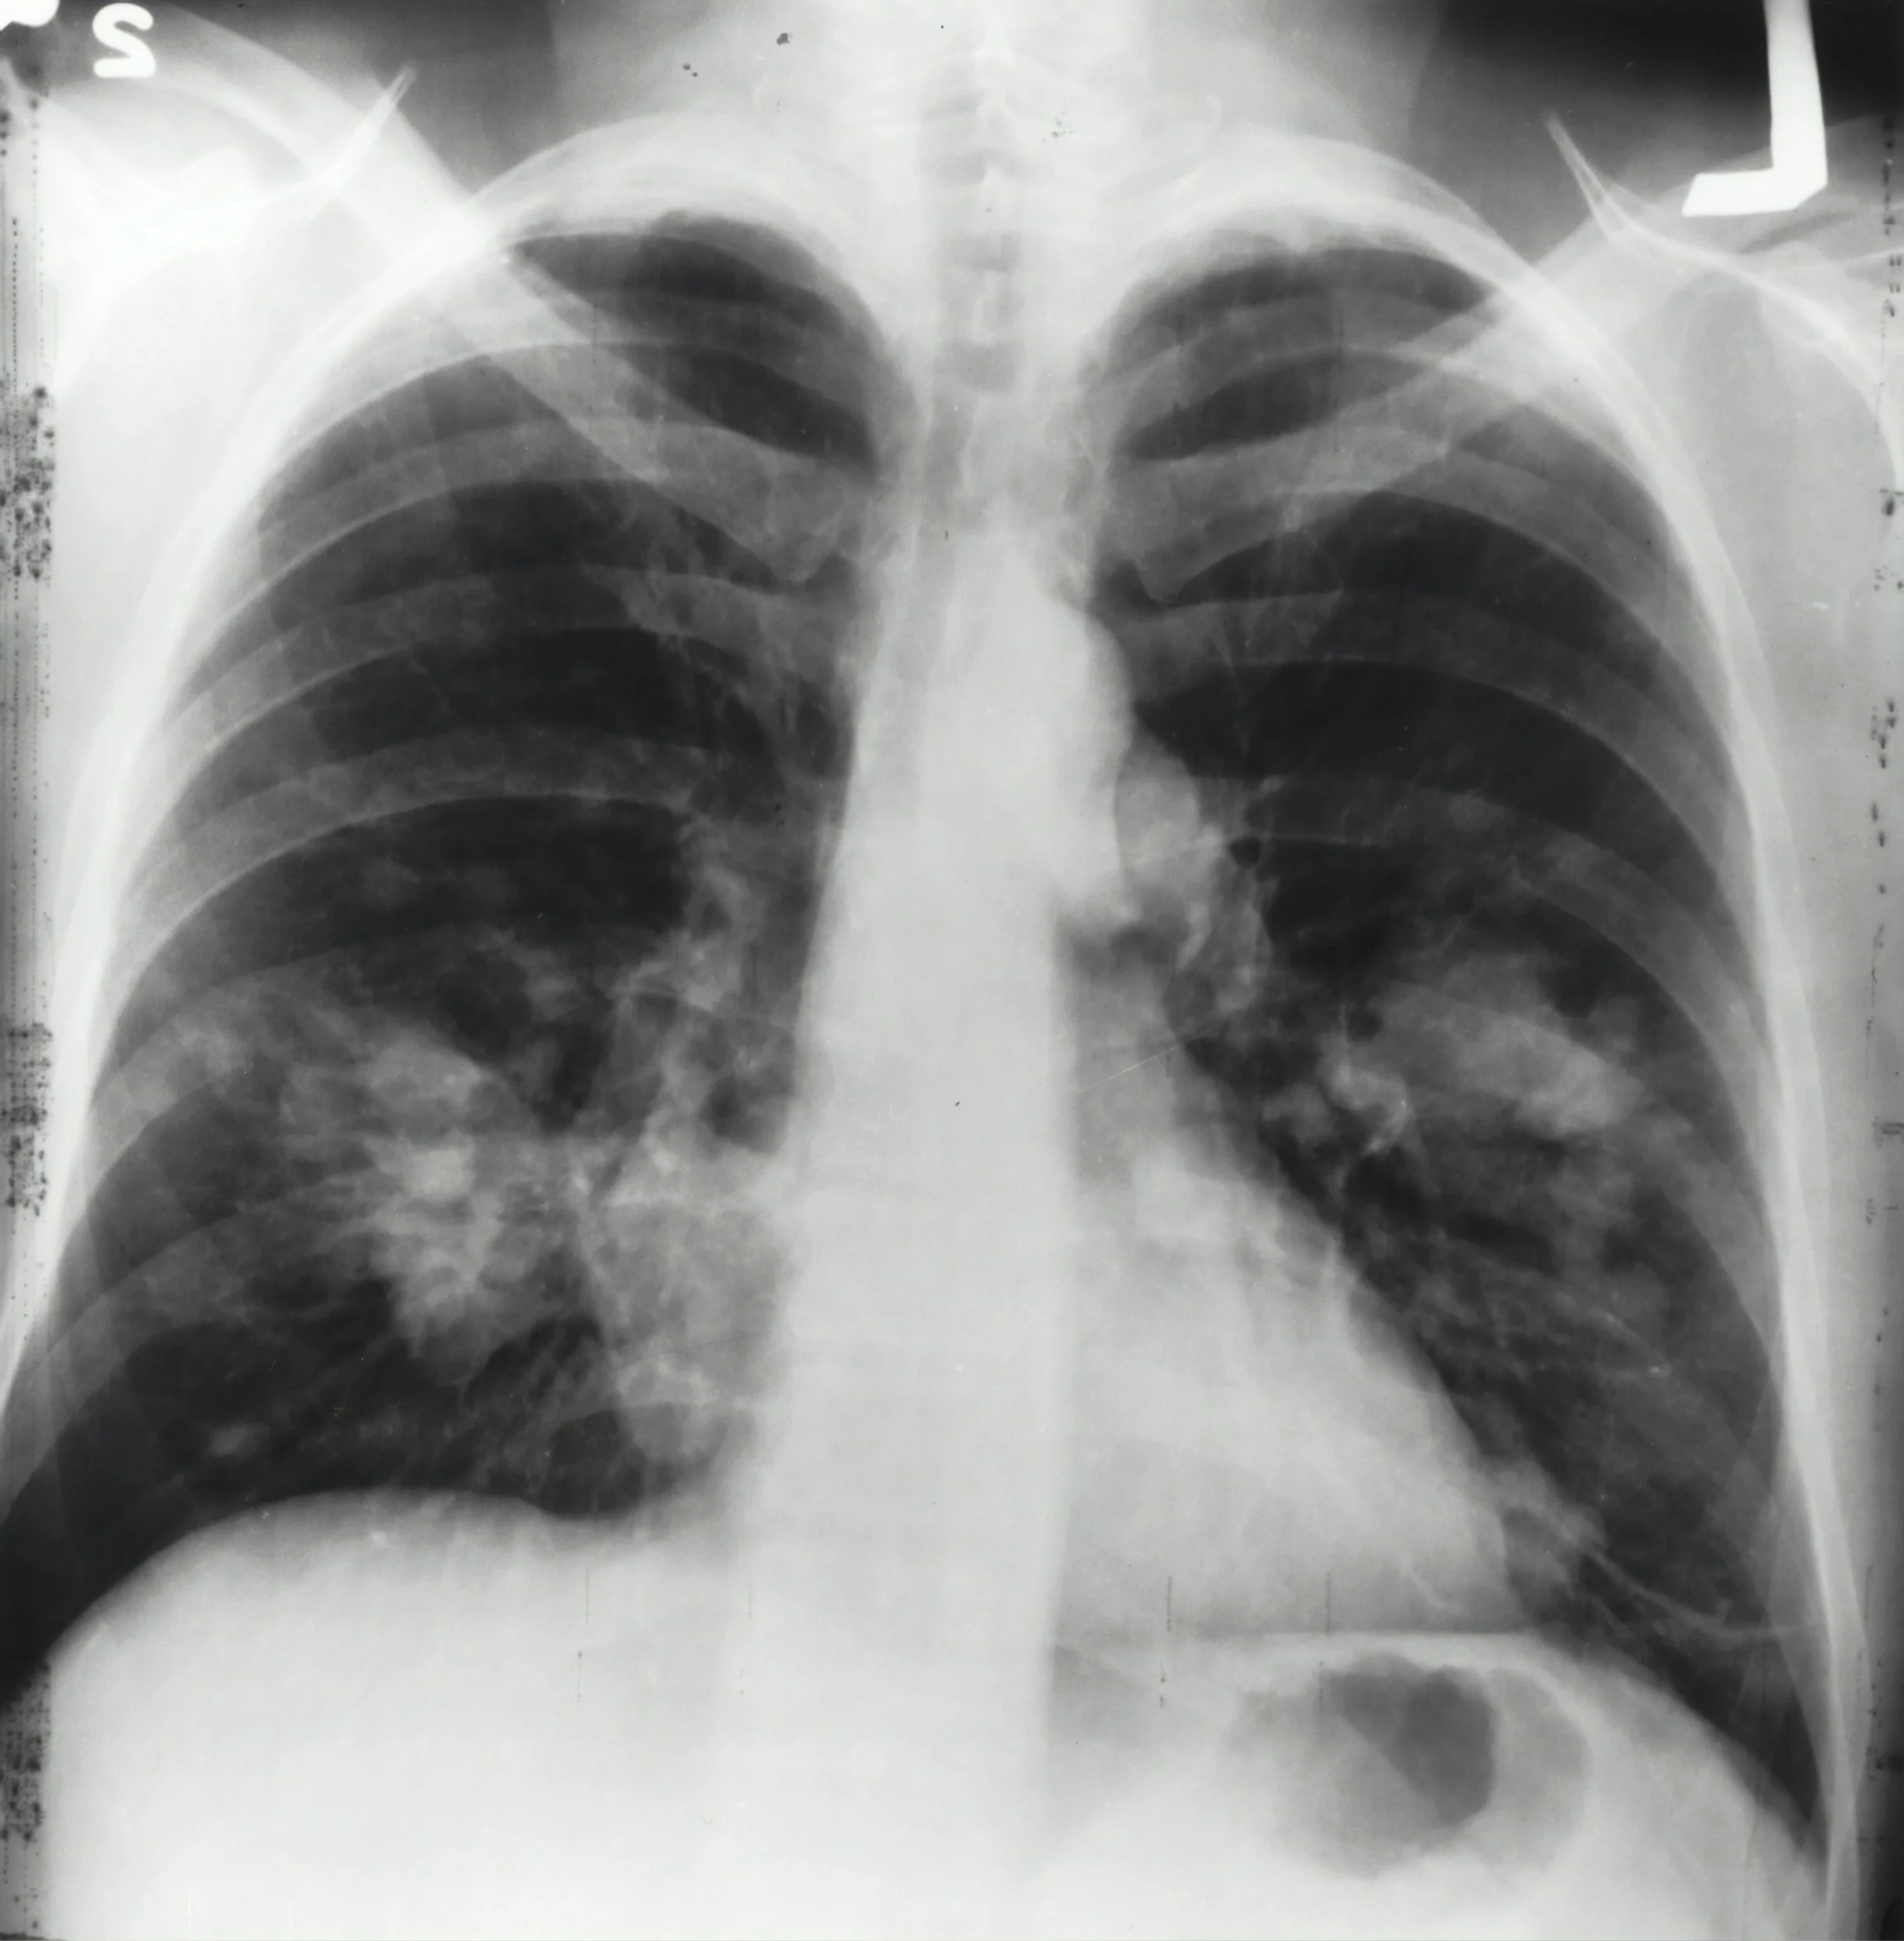

Diagnosing lung cancer can be a multi-step process. It usually involves history taking, listening to symptoms, performing a physical exam and getting blood tests and a chest X-ray. [5]

· Chest X-ray: X-rays can’t diagnose lung cancer — they can only show if there’s something suspicious that they should look into further.

· Imaging: Chest X-rays and CT scans provide images that can show changes in  lungs. PET/CT scans are usually done to evaluate a concerning finding on a CT scan or after a cancer diagnosis to determine whether cancer has spread.